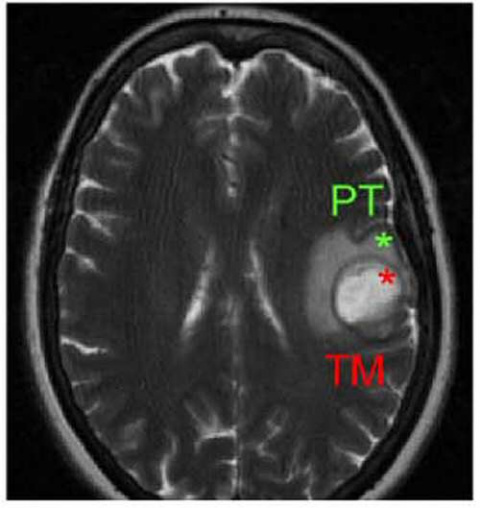

Fruto de una colaboración entre los laboratorios de los profesores de investigación ICREA Ben Lehner y Gian Tartaglia, Benedetta Bolognesi y Andre J. Faure se centraron en la TDP-43, una proteína que se agrega en las neuronas motoras de prácticamente todos los pacientes de ELA. Así, crearon más de 50.000 mutantes de TDP-43 y realizaron un seguimiento de su toxicidad sobre células de levadura. Estos investigadores descubrieron que las formas mutantes que se agregaban, de hecho, eran menos tóxicas que otras versiones de la proteína que, en su lugar, estaban formando unas inusuales especies líquidas en dichas células. “Es exactamente lo contrario de lo que esperábamos”, comenta Lehner, y pone en cuestión muchos de los supuestos existentes en este campo.